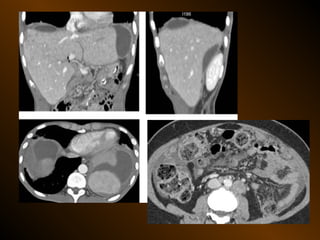

• X QUANG CẮT LỚP ĐIỆN TOÁN

– Mật độ

– Vị trí

– Nguyên nhân

TỤ DỊCH KHU TRÚ

• X QUANG QUY ƯỚC

• SIÊU ÂM

– Mật độ, bắt cản quang ?